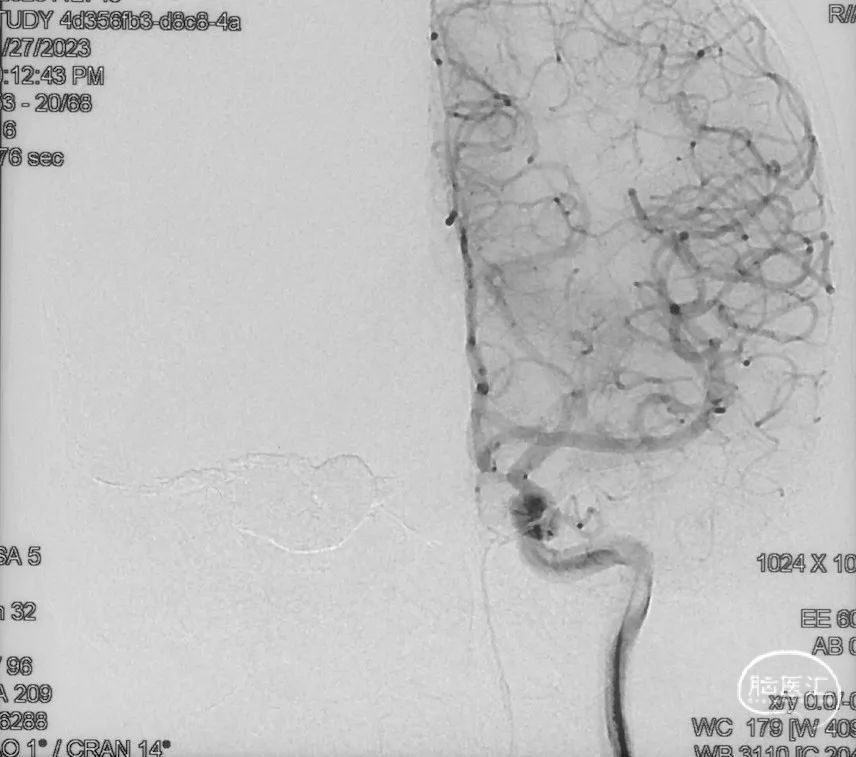

影像学的随访

术后9m

右侧颈内动脉造影未见瘘口显影及静脉早显

右侧颈外动脉造影未见瘘口显影及静脉早显

左侧椎动脉造影未见瘘口显影及静脉早显